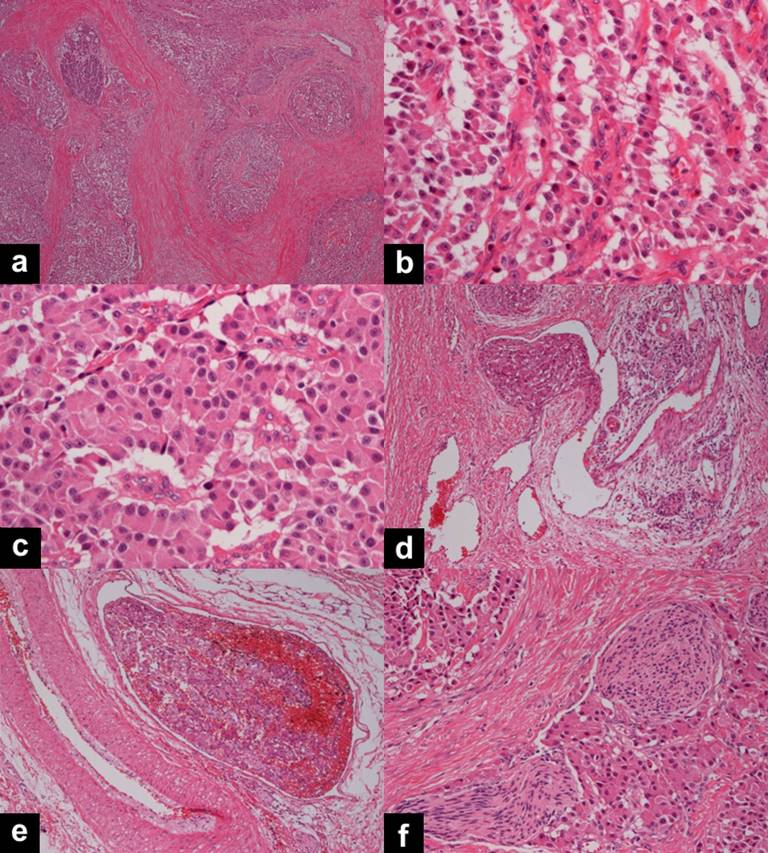

As the preoperative diagnosis, NET or acinar cell carcinoma was considered and pancreaticoduodenectomy was performed. Under the surgical investigation, the pancreatic parenchyma in the head region was displaced by tumor invading the duodenum and lower bile duct. Histologically, the lesion was comprised of small nests and cords of uniform cells arranged in a trabecular or ribbon-like pattern (Figure 3ab). The pseudo-rosette formation (Figure 3c) was seen and the intratumoral stroma had rich fibrosis. Lymphatic, venous and neural invasions (Figure 3def) were observed in the pancreatic head region. Peripancreatic lymph node involvement was also confirmed but there was no neural invasion to the peripancreatic tissues. The pancreatic head tumor directly invaded the MPD, the duodenal muscle and intramucosal lymphatics, but the invasion to the common bile duct was not observed. In the pancreatic body region, the intraductal tumor was connected to the intraductal mass in the head region, and grew within the lumen of the MPD with complete deficiency of the ductal epithelium and proliferation of collagenous tissue of the ductal wall. Immunohistochemically, the tumor cells were positive for chromogranin A and synaptophysin, and negative for insulin, glucagon, somatostatin, gastrin and vasoactive intestinal peptide. The final diagnosis was neuroendocrine tumor, G2.

Figure 3. Histopathological findings (H&E stain). The pancreatic head lesion is comprised of small nests and cords of uniform cells (a.) arranged in a trabecular or ribbon-like pattern (b.). The pseudo-rosette formation (c.) is seen and the intratumoral stroma has rich fibrosis. Lymphatic (d.), venous (e.) and neural invasions (f.) are observed in the pancreatic head region. |